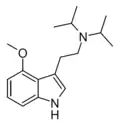

| MiPT | artificial | H | CH3 | CH(CH3)2 | N-Methyl-N-isopropyltryptamine | 96096-52-5 |